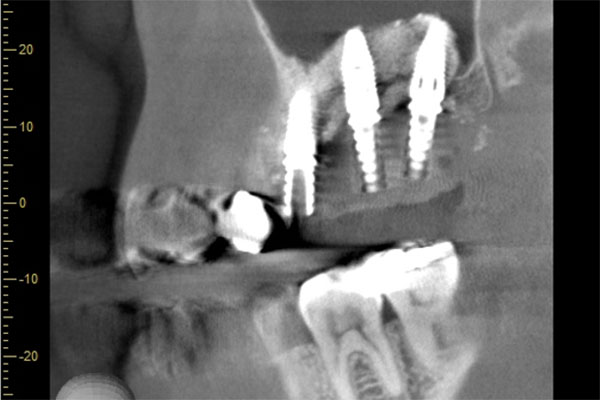

患者様の初診時レントゲン写真

インプラント2本の予定ですので、インプラント同士をほぼ並行に埋入する計画を立てます。神経にインプラントが当たりますと、麻痺が起きたり出血の原因になりますので、

シュミレーション上でもしっかり神経とは距離をおきます。

【担当医師所見】

歯ぐきを切ってインプラントを埋入しました。埋入後は歯ぐきを縫って終わります。

この状態で4ヶ月待ちインプラントと骨の生着を待ちます。

コーンビームCT像を確認すると左側上顎の骨は無くインプラント埋入の際は上顎骨に骨造成が必要と思われたため上顎洞挙上術(サイナスリフト)を併用、インプラント埋入を行うプランとしました。

また欠損部位の大きさを考えるとサージカルガイドの使用が必要と思われたため今回使用した。さらにオペの強度を考え静脈内鎮静法下にてオペを行った。

処置前では黒い透過像(骨が無い)があるが骨造成後1年経過、インプラントテック(仮歯)を入れた際では上顎洞内及びインプラント周囲に白い不透過像(骨がある)が確認できます。